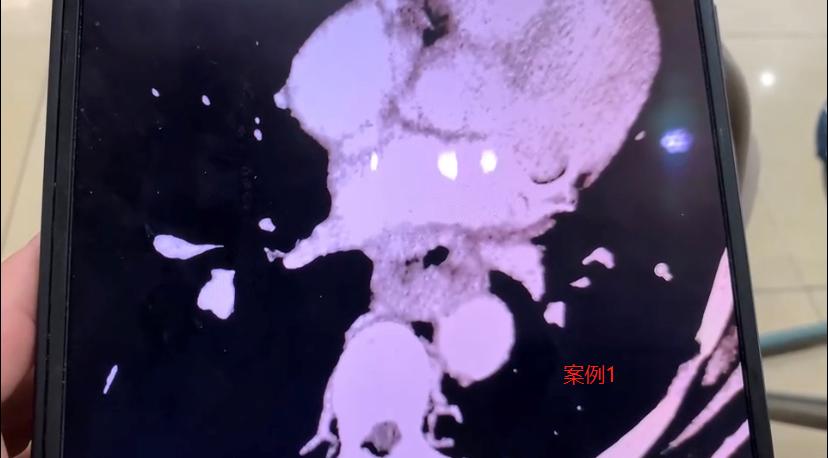

先手术还是先化疗?两位食管癌患者的不同选择,结局差别很大! 1、59岁的大哥,近半年总觉得吃饭堵得慌,一查竟是食管癌,肿瘤有五厘米粗,十几公分长。因为瘤子太大,我建议他先做新辅助治疗——化疗联合免疫治疗,把肿瘤缩小再手术。 但他很坚持,觉得化疗伤身体,反反复复找我一个多月,就是不肯先化疗,说要么直接开刀,要么就不治了。 最后我们尊重他的选择,做了手术。打开之后才发现,肿瘤已经侵犯到心脏心房和下肺静脉,手术做得非常吃力。 虽然顺利切除了,但我心里清楚,他后续的恢复和长期生存,可能会面临更多挑战。 2、66岁的女性患者,情况类似,肿瘤也很大。她儿子半年前找到我,我也建议先做新辅助治疗。他们商量后接受了这个方案。 化疗加免疫治疗起效很明显,肿瘤缩小到几乎看不见,只剩一点残留。不过治疗过程中,患者反应比较重,血小板一直上不来,调养了两个多月才好转。 后来我们做了微创手术,一个多小时就把病灶拿掉了。术后病理结果特别好——肿瘤细胞已经完全找不到了! 我估计,这样规范治疗下来,很有希望实现临床治愈。 这两个病例让我挺有感触的。遇到大病,每个人的性格和选择真的会影响治疗的路。这位女性患者虽然也受了不少罪,但她和家人信任医生、积极配合,终于等到好结果; 而前面那位大哥因为不愿接受前期治疗,后面的路就走得辛苦一些。 其实我想说,生病虽然不幸,但我们不能怕,也别固执。科学应对、积极治疗,才是真正对自己负责。医患同心,很多困难都是可以闯过去的。[谢谢][玫瑰]